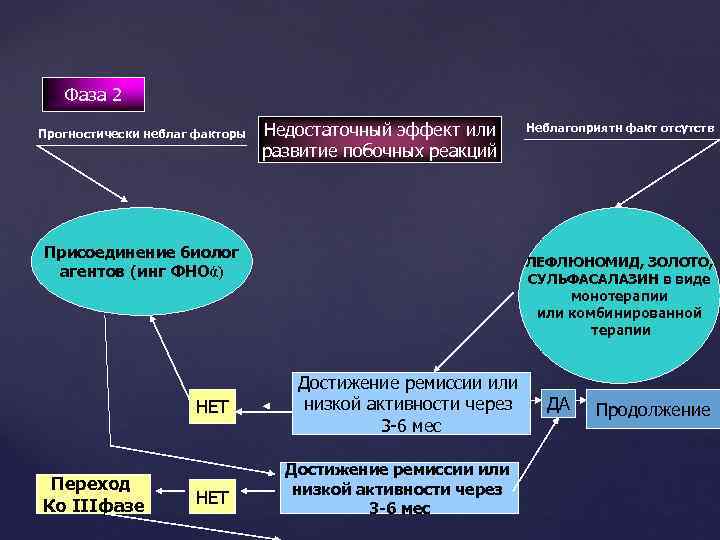

Фаза 2 Прогностически неблаг факторы Недостаточный эффект или развитие побочных реакций Присоединение биолог агентов (инг ФНОά) НЕТ Переход Ко IIIфазе НЕТ Неблагоприятн факт отсутств ЛЕФЛЮНОМИД, ЗОЛОТО, СУЛЬФАСАЛАЗИН в виде монотерапии или комбинированной терапии Достижение ремиссии или низкой активности через 3 -6 мес ДА Продолжение

Фаза 2 Прогностически неблаг факторы Недостаточный эффект или развитие побочных реакций Присоединение биолог агентов (инг ФНОά) НЕТ Переход Ко IIIфазе НЕТ Неблагоприятн факт отсутств ЛЕФЛЮНОМИД, ЗОЛОТО, СУЛЬФАСАЛАЗИН в виде монотерапии или комбинированной терапии Достижение ремиссии или низкой активности через 3 -6 мес ДА Продолжение